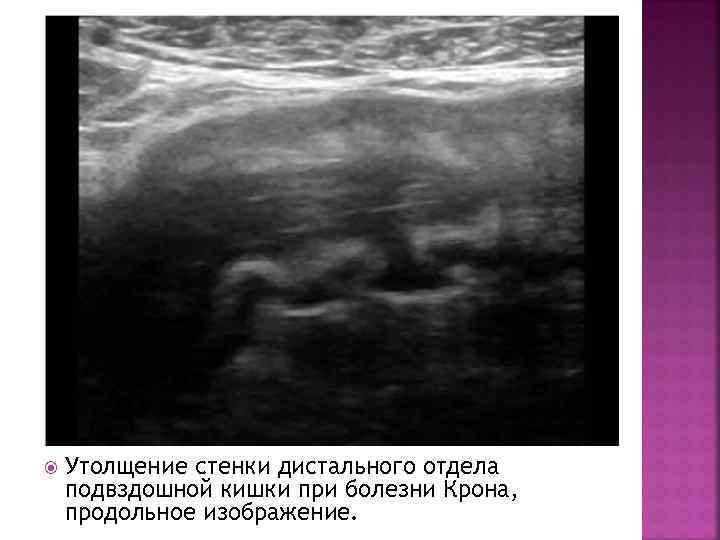

Утолщение стенки дистального отдела подвздошной кишки при болезни Крона, продольное изображение.